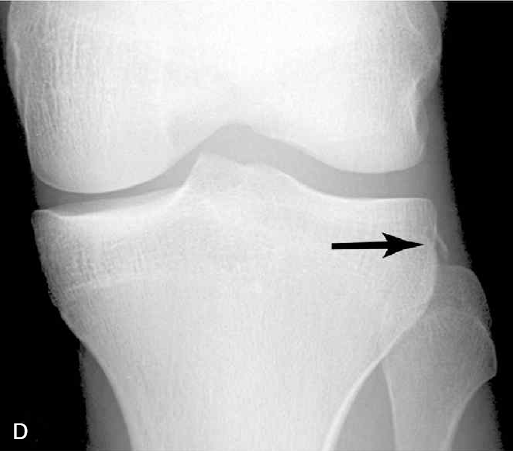

21. Segond 골절이란 무엇이며, 임상적으로 암시하는 바는 무엇인가?

Segond 골절은 외측인대 부착부의 근위 외측 경골의 견열 골절을 말한다. 골절 파편은 매우 작을 수 있다. 방사선 사진 상으로 보기에 매우 힘듦에도 불구하고, 흔하게 전방십자인대 파열과 반월상 연골판 손상이 동반된다.

△ Segond fracture (이미지 출처 : http://www.medicinadurgenza.org/)

△ D는 Segond 골절에 해당. 근위 외측 경골의 견열 골절(화살표)에 해당한다.